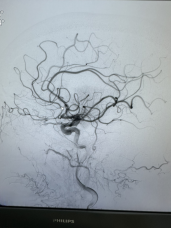

近日,广元市第一人民医院神经内科介入团队成功为91岁高龄患者实施急诊脑血管造影+机械取栓术,及时开通血管,改善了患者的症状。这是医院首次完成91岁超高龄老人急性脑缺血性卒中机械取栓术,老人术后恢复超预期,创造生命奇迹的同时,也再次彰显了医院卒中团队过硬的综合实力。

随即,卒中介入团队快速启动急诊手术流程。11:42,经介入治疗后,梁大爷闭塞血管顺利开通。再次造影显示,患者左侧大脑半球血流恢复。大脑在重新得到新鲜血液灌溉后,因缺血而不完全坏死的脑细胞逐渐恢复生机。